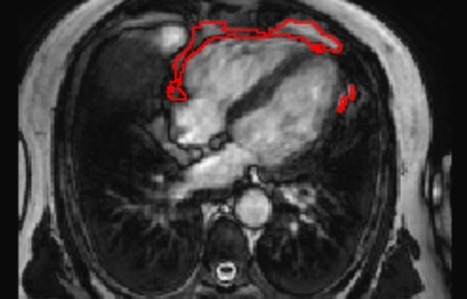

The distribution of fat in the body can influence a person's risk of developing various diseases. The commonly used measure of body mass index (BMI) mostly reflects fat accumulation under the skin, rather than around the internal organs. In particular, there are suggestions that fat accumulation around the heart may be a predictor of heart disease, and has been linked to a range of conditions, including atrial fibrillation, diabetes, and coronary artery disease.

A team led by researchers from Queen Mary University of London has developed a new artificial intelligence (AI) tool that is able to automatically measure the amount of fat around the heart from MRI scan images.

Using the new tool, the team was able to show that a larger amount of fat around the heart is associated with significantly greater odds of diabetes, independent of a person's age, sex, and body mass index.

The research team invented an AI tool that can be applied to standard heart MRI scans to obtain a measure of the fat around the heart automatically and quickly, in under three seconds. This tool can be used by future researchers to discover more about the links between the fat around the heart and disease risk, but also potentially in the future, as part of a patient's standard care in hospital.

The research team tested the AI algorithm's ability to interpret images from heart MRI scans of more than 45,000 people, including participants in the UK Biobank, a database of health information from over half a million participants from across the UK.

The team found that the AI tool was accurately able to determine the amount of fat around the heart in those images, and it was also able to calculate a patient's risk of diabetes